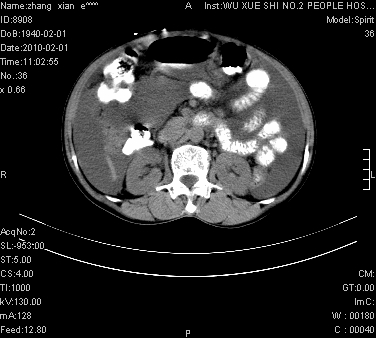

标题: CT24434:70岁 女 腹胀,腹水原因待查 [打印本页]

标题: CT24434:70岁 女 腹胀,腹水原因待查

大量腹水,脾脏囊性占位,子宫颈占位,右侧腹股沟淋巴结肿大,建议+c,先查妇科。

腹盆腔大量积液,子宫增大,子宫颈增大外形不规则,内见低密度影,膀胱后壁显示不清,右腹股沟肿大淋巴结,脾脏囊性占位,子宫颈占位,子宫颈癌?建议增强。

子宫、宫颈占位?转移性腹水?肝性腹水?脾脏囊性占位,囊肿?血管瘤?淋巴瘤?

考虑:1、腹膜转移,大量腹水;

2、脾占位性病变;

3、左侧卵巢占位性病变,建议增强进一步检查。

大量腹水,右肾、脾囊肿可能性大          考虑左侧附件区占位,建议增强